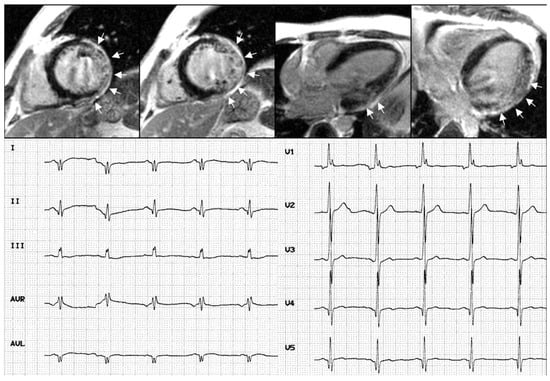

- De Ambroggi, L.; Raisaro, A.; Marchiano, S.; Radice, S.; Meola, G. Cardiac involvement in patients with myotonic dystrophy: Characteristic features of magnetic resonance imaging. Eur. Heart J. 1995, 16, 1007. [Google Scholar] [CrossRef]